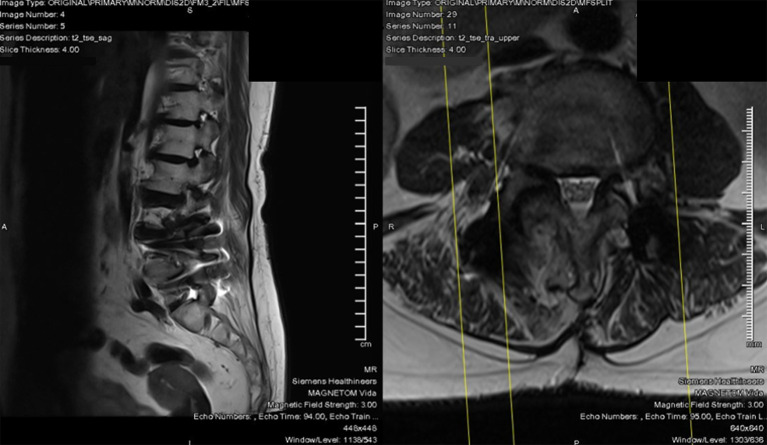

Case description: A 69-year-old woman with a prior L4/L5 TLIF presented to the clinic with a new onset of right lower limb radiculopathy along the L3 dermatome, as well as numbness in the L2 distribution. Magnetic resonance imaging (MRI) studies revealed adjacent segment degeneration in L2/L3 and L3/L4, with disc-osteophyte complexes impinging onto the exiting L2 and L3 nerve roots, respectively. We opted for a right L2/L3 and L3/L4 unilateral endoscopic biportal transforaminal decompression. The surgery was successful, with the patient being discharged from the hospital on postoperative day 1 with minimal pain. Within 2 weeks, the patient described significant improvement in both back pain and radiculopathy, and the numbness had completely resolved. Oswestry Disability Index was used to objectively quantify outcomes and saw an improvement from 15 to 0. Notably, there were no complications.